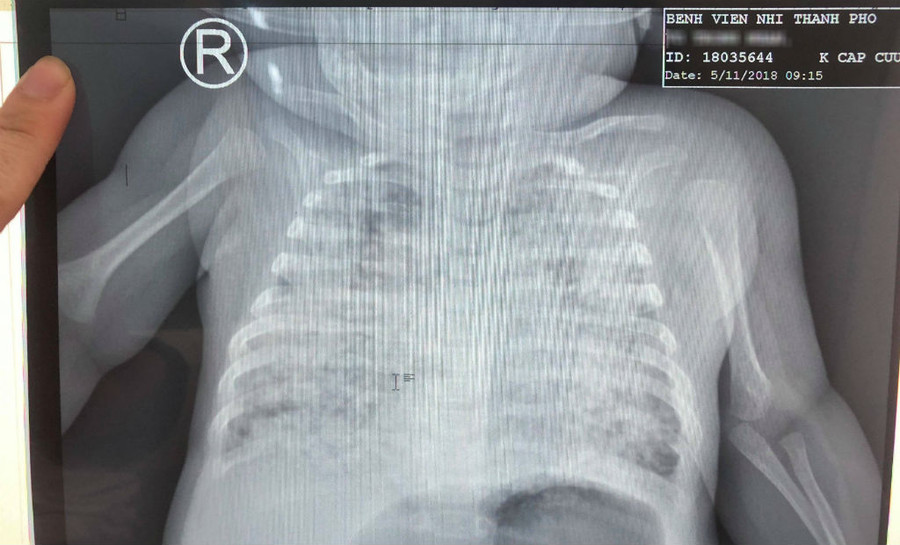

| Phổi bệnh nhi trắng xóa quá phim chụp Xquang |

Theo BS, phổi của bé trai trắng xóa, kén khí do các ổ lao vỡ tấn công khiến bệnh nhi bị tràn phổi 4 lần, suy hô hấp nặng, phải thở máy liên tục.

Để giải quyết triệt để từng đợt nhiễm trùng phổi cho bé, bác sĩ tiến hành chọc hút khí màng phổi nhiều lần khi kén lao vỡ.

Có lúc, tình trạng bé nguy kịch, phải thở máy rung tần số cao để đảm bảo trao đổi khí, kết hợp điều trị kháng sinh và kháng lao tấn công suốt 3 tháng.

Qua 90 ngày điều trị tích cực, sức khỏe bé ổn định, phổi sáng dần lên. Mô phổi giảm tổn thương và thông khí ngày càng hiệu quả, các kén khí lớn giảm rõ rệt.